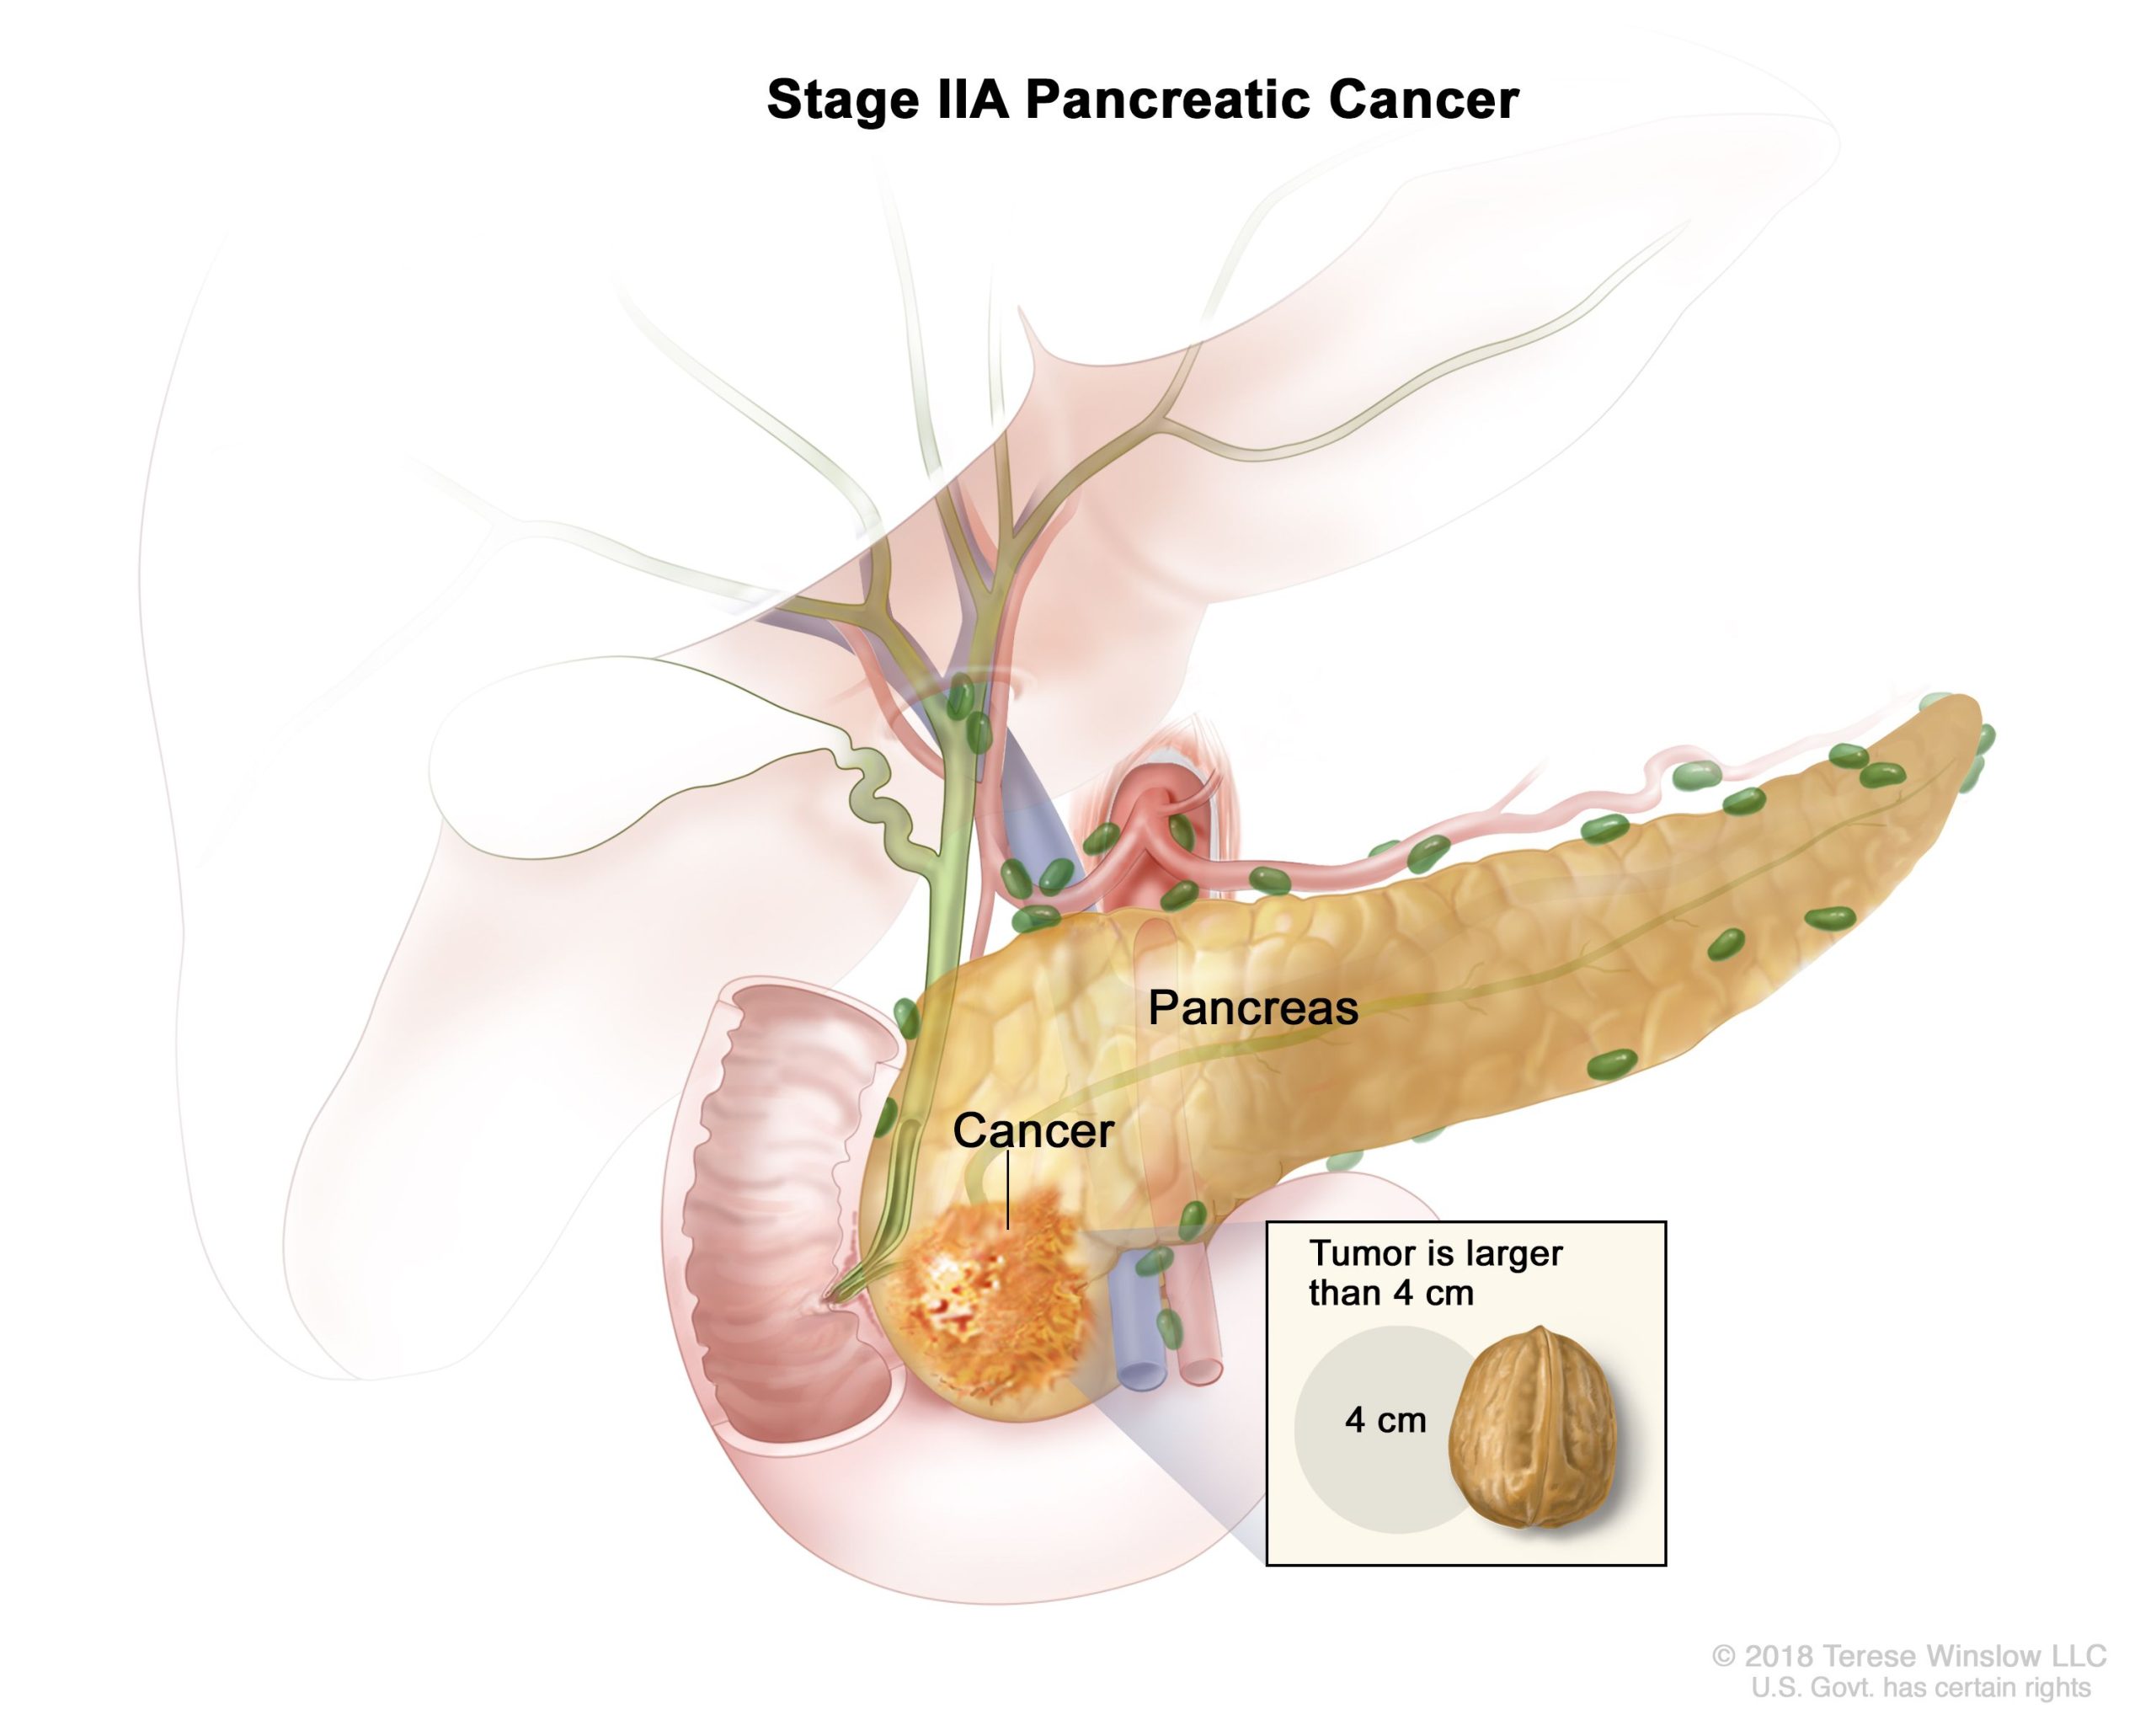

Pancreatic cancer begins in the tissues of your pancreas — an organ in your abdomen that lies behind the lower part of your stomach. Your pancreas releases enzymes that aid digestion and produces hormones that help manage your blood sugar.